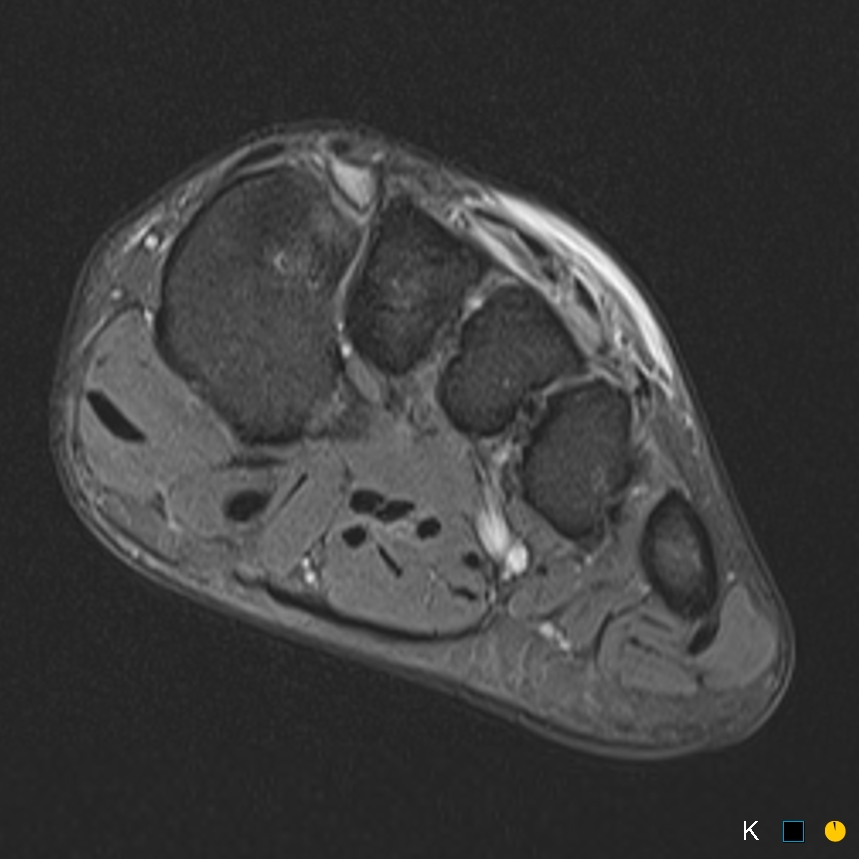

Sprinter. Dorsal midfoot pain

Symptomatic os intermetatarseum

Classification: free standing, articulating and fused

Case reports of symptomatic os intermetatarseum in athletes

Symptoms may relate to compression medial br DPN